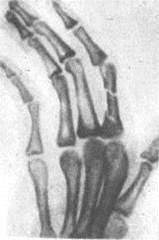

При переломах фаланг наблюдаются обычные признаки переломов костей: припухлость и кровоизлияние в области перелома, наличие деформаций, болезненность при пальпации области перелома и нарушение функции поврежденного пальца. Все эти признаки имеются при смещении отломков. Выраженная деформация отсутствует при переломах без смещения (рис.6, 7), трещинах и внутрисуставных повреждениях (9, с.89).

Рисунок 6 - Внутрисуставной перелом средней фаланги пальца.

Рисунок 7 - Перелом основной фаланги РЖРЖ пальца (а) и двойной перелом (б).